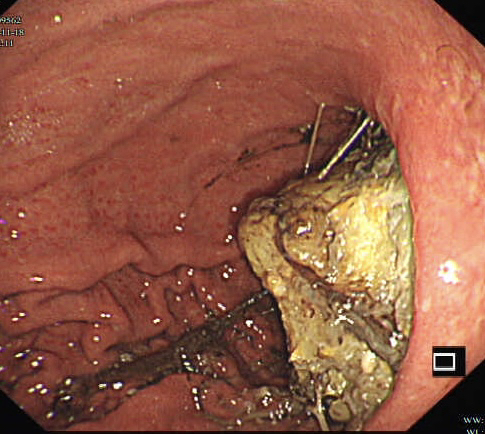

胃镜证实

同样治疗后痊愈出院